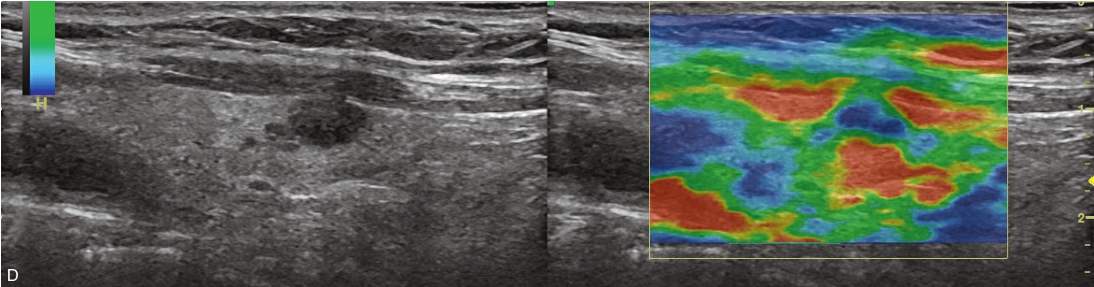

甲状腺右叶下极可见一低回声结节,紧贴甲状腺包膜,突出于甲状腺包膜,大小约0.82cm×0.72cm×0.55cm,呈椭圆形,边界清楚,内部为低回声,分布不均匀,后方回声稍增强,CDFI显示结节内未见明显血流信号,弹性成像示弹性评分为3分,见图1-3-11。

图1-3-11 甲状腺“木乃伊”结节

A、B、C、D.甲状腺“木乃伊”结节常规超声图像

经肘正中静脉团状注射造影剂SonoVue1.2ml后,13s周围甲状腺组织开始增强,病灶边缘部呈稍增强,病灶内部始终呈无增强,在整个造影过程中病灶内始终呈无增强,见图1-3-12、ER1-3-6。

“木乃伊”结节超声造影表现为无增强。

部分良性甲状腺结节囊液吸收后超声表现为低回声、缩小,超声表现为可疑恶性征像,二维超声表现与甲状腺乳头状癌难以鉴别,超声造影可以明确病灶内有无增强,提高诊断准确性。

图1-3-12 甲状腺“木乃伊”结节造影图像

A.造影示低回声结节呈无增强;B.增强晚期仍呈无增强